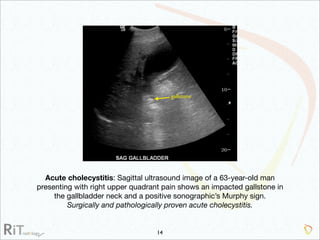

The document discusses the imaging modalities used in evaluating acute abdominal pain, including radiography, ultrasound, computed tomography (CT), and scintigraphy, highlighting their roles, indications, and limitations. It emphasizes the complexity of diagnosing acute abdomen due to its broad differential diagnoses and the necessity for accurate imaging to inform timely management. Additionally, the document outlines considerations such as patient history, contrast medium reactions, and appropriate imaging criteria based on various clinical presentations.